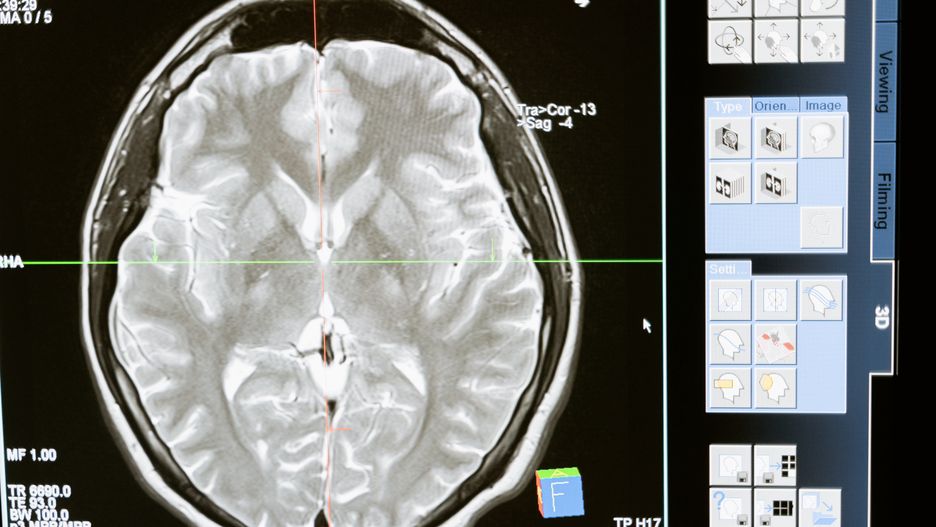

W prowincji Nowy Brunszwik w Kanadzie od jakiegoś czasu lekarze obserwują tajemniczą chorobę neurologiczną. Dotyka ona głównie młodych ludzi, u których występuje szereg niepokojących objawów. Oficjalnie liczba przypadków się nie zwiększa, ale są obawy, że na tajemniczą chorobę zapada coraz więcej osób.

Tajemnicza choroba neurologiczna, która od ponad dwóch lat niepokoi ekspertów, dotyka coraz większą liczbę młodych ludzi. Pracownik Vitalité Health Network, jednego z dwóch organów ds. zdrowia w kanadyjskiej prowincji Nowy Brunszwik, w rozmowie z "Guardianem" powiedział, że liczba podejrzanych przypadków rośnie.

U młodych dorosłych, którzy wcześniej nie mieli problemów zdrowotnych, pojawia się szereg niepokojących objawów. Zalicza się do nich m.in. szybką utratę wagi, bezsenność, halucynacje, trudności w myśleniu i ograniczoną zdolność ruchową.

Oficjalna liczba przypadków objętych dochodzeniem (48) pozostaje niezmienna, odkąd została po raz pierwszy ogłoszona wiosną 2021 r. Wiele źródeł twierdzi jednak, że tajemnicza choroba mogła dotknąć nawet 150 osób.

Na chorobę mogą mieć wpływ czynniki środowiskowe. Odnotowano co najmniej dziewięć przypadków wystąpienia objawów u osób pozostających w bliskim kontakcie z chorymi.

To nie jest choroba Nowego Brunszwiku. Prawdopodobnie jesteśmy obszarem, który podnosi alarm, ponieważ mieszkamy głównie na wsi i w obszarze, w którym ludzie mogą być bardziej narażeni na czynniki środowiskowe - wyjasnił pracownik Vitalité Health Network.